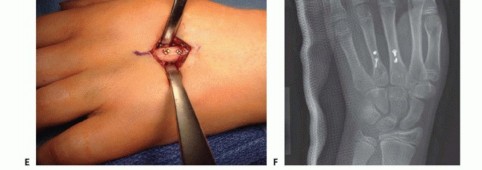

TECH FIG 6 • A,B. Intra-articular head fracture of the fourth metacarpal. C. Dorsal approach to an MP joint. Extensor tendon beneath top retractor. Capsule grabbed by pickup forceps. Articular cartilage seen deep to capsule. D,E. Intra-articular fracture stabilized with headless screws. (continued)

TECH FIG 6 • (continued) F,G. Intra-articular head fracture stabilized with extra-articular screws.